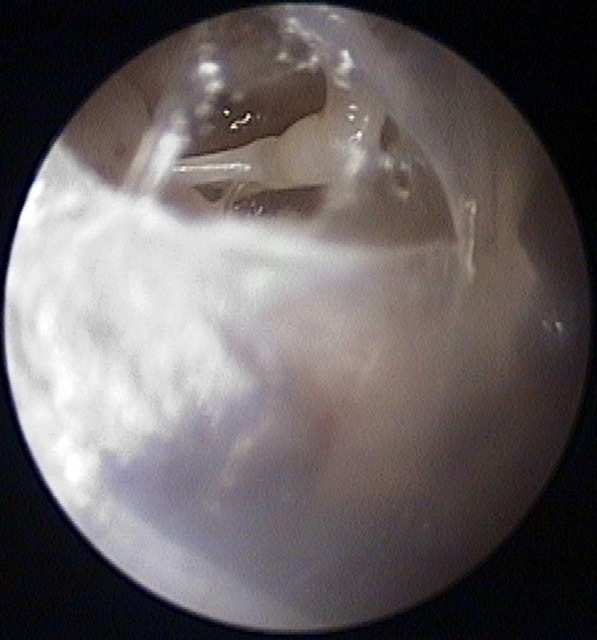

Perforation